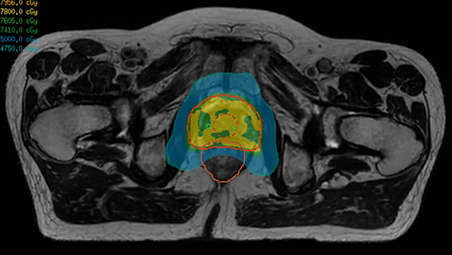

Whether for external beam radiation therapy (RT) or brachytherapy, integrating MR imaging into CT‑based planning can harness the power of MRI and transform patient management. With MRI’s excellent soft-tissue contrast, you can clearly see the tumor and organs at risk. So you can support accuracy in delineation and design the best possible treatment plans. Image courtesy of William Beaumont Health System, Detroit, USA - A superb MRI platform for radiation oncology

Enjoy consistent, excellent image quality for multiple anatomies. Versatile arrangements of dStream coils work together with ExamCards tailored for RT to provide high-contrast images with high geometric fidelity. Quickly execute complete imaging protocols for prostate, female pelvis, brain, head and neck, and spine. - Learn and share MRI expertise

Our innovative MRCAT (MR for Calculating ATtenuation) clinical applications lets you plan radiation therapy using MRI as primary imaging modality. Within just one, fast MR exam, MRCAT provides both excellent soft-tissue contrast for target and OAR delineation and CT-like density information for dose calculations. This not only extends the benefits of MRI’s excellent soft-tissue contrast to radiotherapy planning, but it also eliminates arduous, error-prone CT-MRI registration from the process, reducing uncertainties and complexity. Check out the related product section for the clinical application areas.

Whether for external beam radiation therapy (RT) or brachytherapy, integrating MR imaging into CT‑based planning can harness the power of MRI and transform patient management. With MRI’s excellent soft-tissue contrast, you can clearly see the tumor and organs at risk. So you can support accuracy in delineation and design the best possible treatment plans. Image courtesy of William Beaumont Health System, Detroit, USA - A superb MRI platform for radiation oncology

Enjoy consistent, excellent image quality for multiple anatomies. Versatile arrangements of dStream coils work together with ExamCards tailored for RT to provide high-contrast images with high geometric fidelity. Quickly execute complete imaging protocols for prostate, female pelvis, brain, head and neck, and spine. - Learn and share MRI expertise

Our innovative MRCAT (MR for Calculating ATtenuation) clinical applications lets you plan radiation therapy using MRI as primary imaging modality. Within just one, fast MR exam, MRCAT provides both excellent soft-tissue contrast for target and OAR delineation and CT-like density information for dose calculations. This not only extends the benefits of MRI’s excellent soft-tissue contrast to radiotherapy planning, but it also eliminates arduous, error-prone CT-MRI registration from the process, reducing uncertainties and complexity. Check out the related product section for the clinical application areas.

Our innovative MRCAT (MR for Calculating ATtenuation) clinical applications lets you plan radiation therapy using MRI as primary imaging modality. Within just one, fast MR exam, MRCAT provides both excellent soft-tissue contrast for target and OAR delineation and CT-like density information for dose calculations. This not only extends the benefits of MRI’s excellent soft-tissue contrast to radiotherapy planning, but it also eliminates arduous, error-prone CT-MRI registration from the process, reducing uncertainties and complexity.